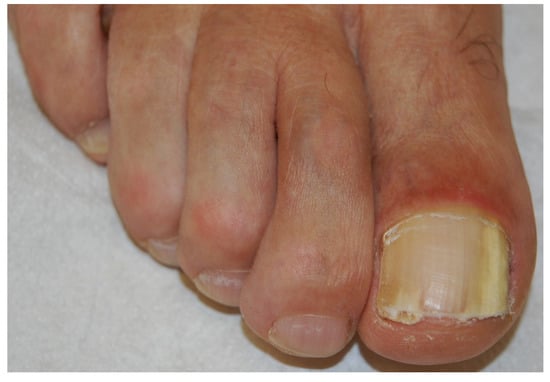

Fungi reach the nail through the hyponychium and invade the undersurface of the nail unit plate spreading proximally. Distal and lateral subungual onychomycosis (DLSO) usually affects one or both of the great toenails and is also usually associated with tinea pedis [7]. The nail plate appears yellow-white, is detached due to onycholysis, with distal subungual hyperkeratosis (Figure 1). Less frequently, a brown, black or orange discoloration of the onycholytic nail can be seen (Figure 2). A possible presentation of DLSO due to dermatophytes is dermatophytoma, a subungual accumulation of hyphae and scales, scarcely reached by antifungals, which require excision of the area and systemic treatment. DLSO may be associated with black pigmentation of the nail (“fungal melanonychia”) (Figure 3), when the pathogen is the Melanoides variant of Trichophyton rubrum or other fungi that produce melanin, like Neoscytalidium dimidiatum or Aspergillus niger [11]. Onychomycosis due to non-dermatophytes is typically associated with a marked periungual inflammation (Figure 4). Differential diagnoses of DLSO include traumatic onycholysis (usually symmetrical and subungual hyperkeratosis is absent) and nail psoriasis (diffuse hyperkeratosis, several/all toenail involved, others skin and nail signs of psoriasis).

Figure 1. Distal and lateral subungual onychomycosis (DLSO): whitish discoloration, onycholysis and subungual hyperkeratosis.